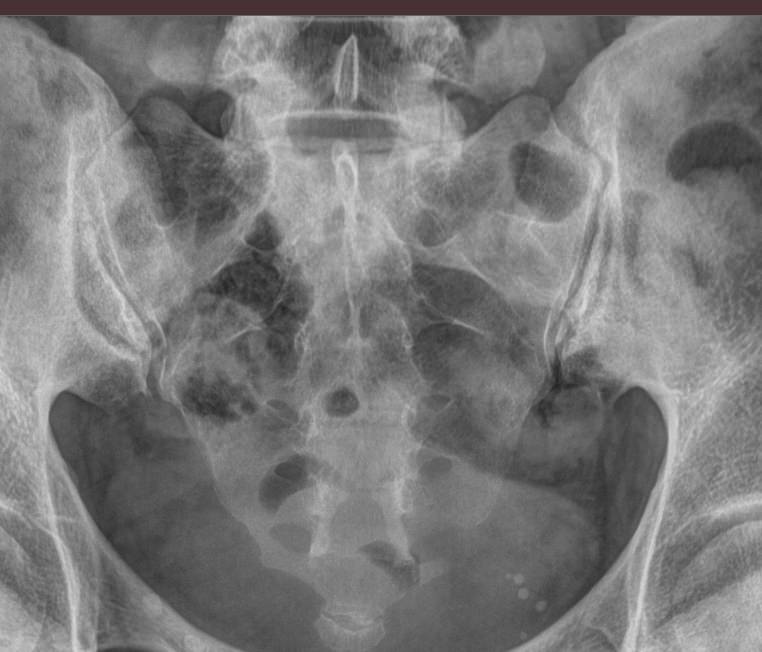

Для диагностики сочленения прибегают к рентгенографии, причем снимки делают с обеих сторон, чтобы можно было сравнить здоровую и измененную сторону. Для более детального исследования применяют МРТ.

Что покажет рентген крестцово-подвздошного сочленения?

• Изменения в состоянии рентгеновской суставной щели ― расширение, сужение, сращение;

• Изменения суставной поверхности ― нечеткость контуров, уплотнение, эрозии;

• Изменения в костной ткани ― участки деструкции, воспаление, склероз;

• Наличие кист и других новообразований;

• Изменения в мягких тканях